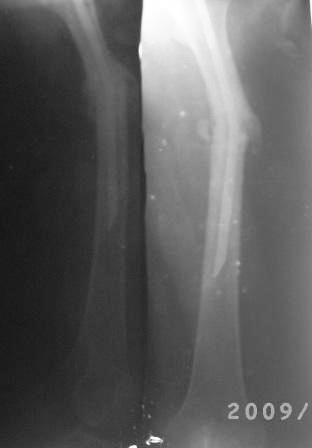

12.02.09г б-ная оперирована: з/остеоклазия (без особого труда- видимо тугой ложный сустав) коррекция деформации, удаление штифта из надвертельной обл, рассверливание канала гибкими развертками, реостеосинтез блокируюшим гвоздем Д-11мм.

Но я впервые почувствовал такую сильно ОСТЕОПОРОТИЧНУЮ кость, что блокируюшие винты проваливаются внутрь кости, что винты можно ввести без сверления кости, и что винты провинчиваются холостую, т.е. не стабильно.

P.S. Снимки не качественные, извиняюсь! последний снимок ЭРГА, два снимка объединил.

Я заранее приношу свои извинения, но по демонстрации видно, что сама методика БИОС использована с нарушениями. Да я с Вами согласен и сам часто встречался подобными случаями, когда из-за отсутствия функции конечности (опорной и двигательной) поврежденный сегмент теряеть минеральную плотность, тем самым развивается остеопороз. Однако Вам надо было заранее учитывать эти моменты и дистальные винты надо было установить четко бикортикально, в Вашем случае верхний дистальный винт короткий, нижний дистальный винт вне отверстия, в таком расположении он никак не может быть в блокирующем отверстии. Ранняя опорная нагрузка зависит от стабильности синтеза, веса пациента, но в любом случае дозированная нагрузка (собственный вес конечности) нужна, иначе срастить ложный сустав и ликвидровать остеопороз невозможно (кость должна выполнять свою функцию). С уважением Ерсин Жунусов.